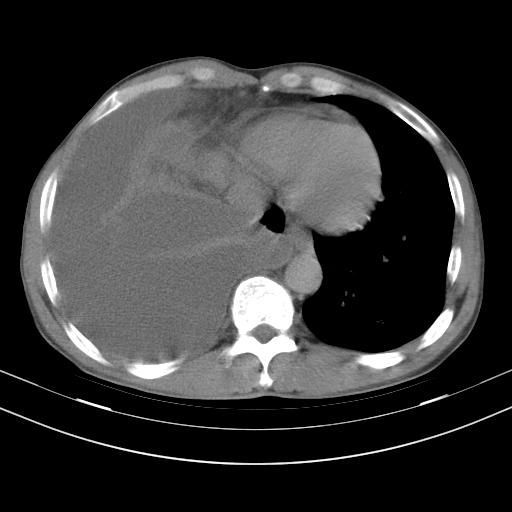

男性,44岁,结核病史多年。现胸闷气短,咳嗽,偶咳血。

1、右侧大量胸腔积液伴右肺压缩性膨胀不全,建议抽液治疗后复查 2、两肺继发性tb伴空洞形成。

1)两肺继发性肺结核伴空洞形成,左肺多发性结核球。2)右侧大量胸腔积液伴右肺部分膨胀不全。3)纵隔淋巴结肿大。

吉大一院胸水抽检结果:结核性胸水

结核性胸水——结核性胸膜炎 感谢楼主反馈结果